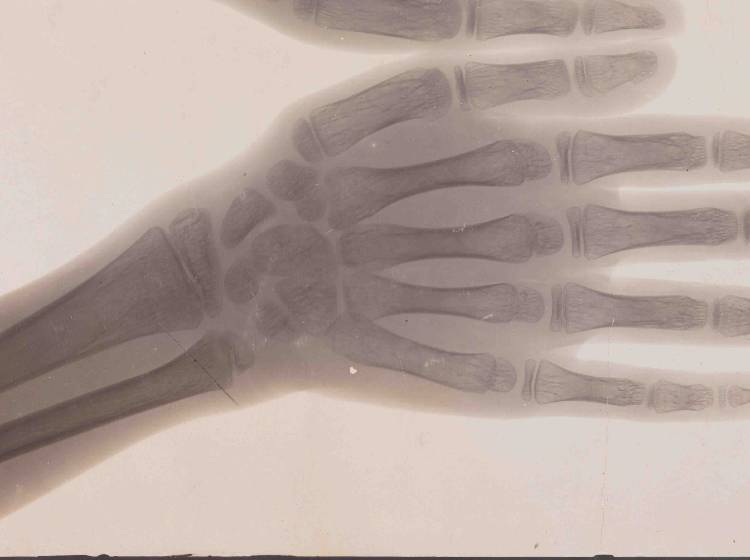

Selbst geschädigt hat sich auch Guido Holzknecht. Der Arzt, Jahrgang 1872, führte die Röntgenologie in Wien ein und erfand ein Röntgendosiergerät. Er schädigte seine Hand in Selbstversuchen dauerhaft, worauf sie Stück für Stück amputiert werden musste. Der Rest von Holzknechts rechter Hand ist ausnahmsweise Teil der Ausstellung, weil er sein Einverständnis gab. Üblicherweise wird auf Anonymität Wert gelegt, wird in der Ausstellung auch auf die ethischen Probleme bei der Nutzung von Körperteilen als Museumsstücke hingewiesen. Patienten um Zustimmung zu fragen, war laut Winter lange nicht üblich.

Ein weiteres Einsatzgebiet von Röntgengeräten waren Schuhgeschäfte. Die Idee kam in den 1920er-Jahren aus den USA und sollte helfen, exakt sitzende Schuhe an Kinderfüße anzupassen. Erst nach 1950 gab es erste Warnungen vor den Röntgengeräten, deren Strahlung Kunden und Personal unkontrolliert traf. Die sogenannten Pedoskope waren noch 20 Jahre später im Einsatz. Inzwischen sind Röntgenstrahlen, entdeckt von Wilhelm Conrad Röntgen, ein wichtiges, nicht-invasives Instrument zur Abbildung von Knochen und inneren Organen.